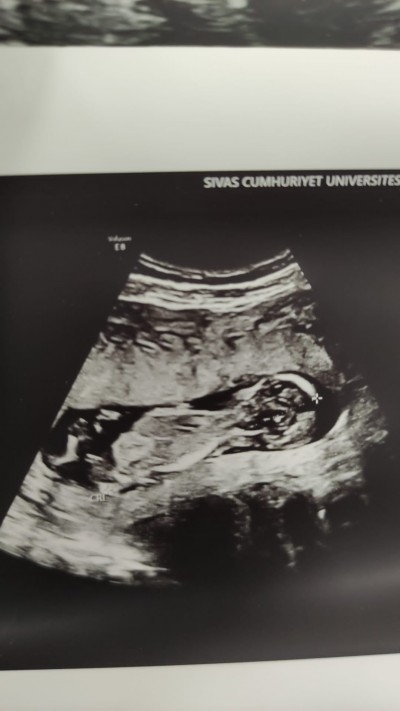

Cinsiyet tahmini anlayan varmı gebelik haftası 13+3 :)

image